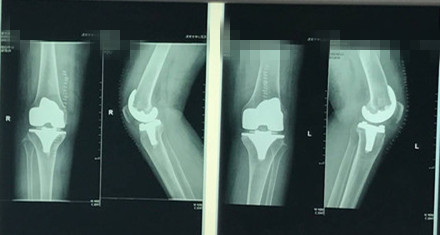

5月10日和5月24日,胡洪波副主任医师分两次为雷大妈分别置换了两侧膝关节,每次手术约90分钟,术中出血量在100毫升左右。

第二侧膝关节换好后的第3天,雷大妈就下地了,第10天完全扔掉了拐杖,行走活动大致恢复正常,生活完全能自理。